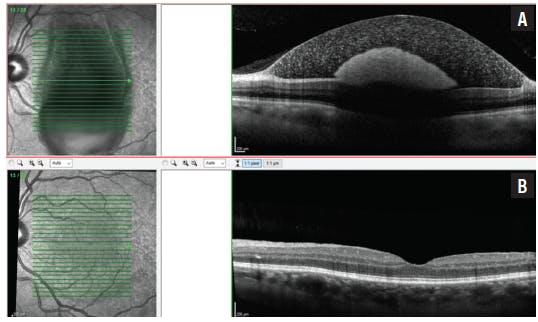

On mydriatic fundoscopy, no alteration was found in the right eye. A macular retinal hemorrhage was seen in the left eye at the superotemporal arcade, with a suspected preretinal component within a gravitational tract including and hiding the inferior temporal arcade. Also noted were four other smaller intraretinal hemorrhages symmetrically positioned in each of the four vascular arcades. The retina was fully attached 360°, and no other alterations were found, including on the optic disc, apart from mild vascular tortuosity and mild fundus tessellation. Vitreous hemorrhage was absent (Figure 1).

The spectral-domain OCT (SD-OCT) revealed no alterations in the right eye and what appeared to be a detached inner limiting membrane (ILM) in the left eye at the foveal region, with a hyperreflective area compatible with blood within the sub-ILM space and with posterior shadowing.

One month after the procedure, the patient’s VA had improved to 20/20 OS. Fundoscopy revealed the absorption of the smaller hemorrhages and the absence of blood within the macular area, with no new findings. Macular SD-OCT revealed no alterations in the right eye (Figure 2). In the left, a patent foveal depression was seen, with rare intraretinal hyperreflective dots and without signs of internal or external retinal or vitreoretinal interface alterations (Figure 3).